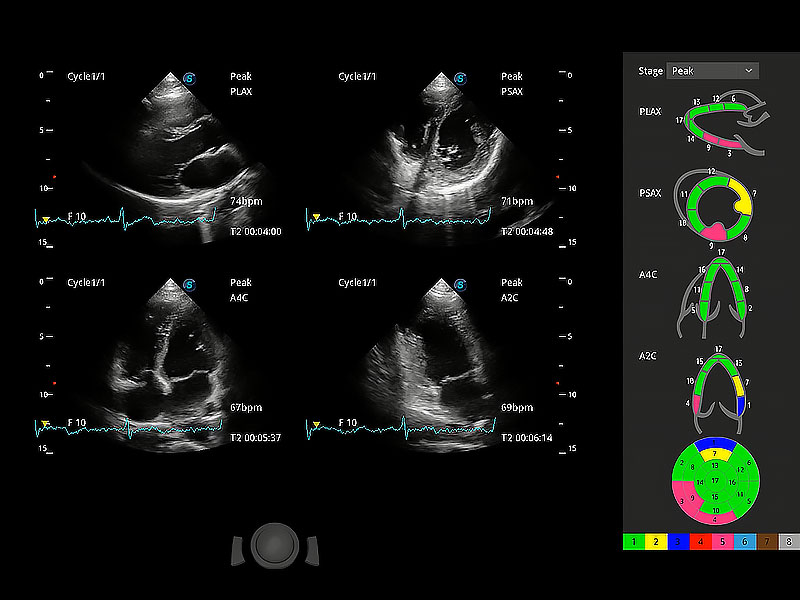

ProPet 80 配備了豐富的心臟探頭群、先進(jìn)的成像技術(shù)和專業(yè)的心臟測量工具,可幫助動物醫(yī)生為不同體型和生理結(jié)構(gòu)的動物提供心臟和心肌功能的全面評估。

通過心肌識別技術(shù)與二維斑點(diǎn)追蹤技術(shù)相結(jié)合,對心臟的超聲圖像進(jìn)行量化分析。計算心肌17個節(jié)段的應(yīng)變、應(yīng)變率、速度、位移等,并通過牛眼圖的形式進(jìn)行呈現(xiàn)。

具備多種協(xié)議可選,同時支持17階段劃分法和專業(yè)的SE報告。